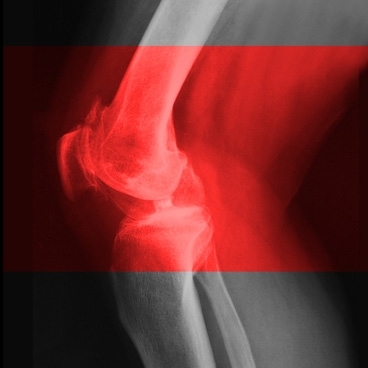

About 27 million Americans suffer from arthritis, and more than three million of those cases result from a joint injury, often in the knee, that provokes slow and steady cartilage deterioration.

A new study from MIT suggests that a steroid drug currently used to treat inflammatory diseases could also prevent osteoarthritis from ever developing in those people, if given soon after the injury.